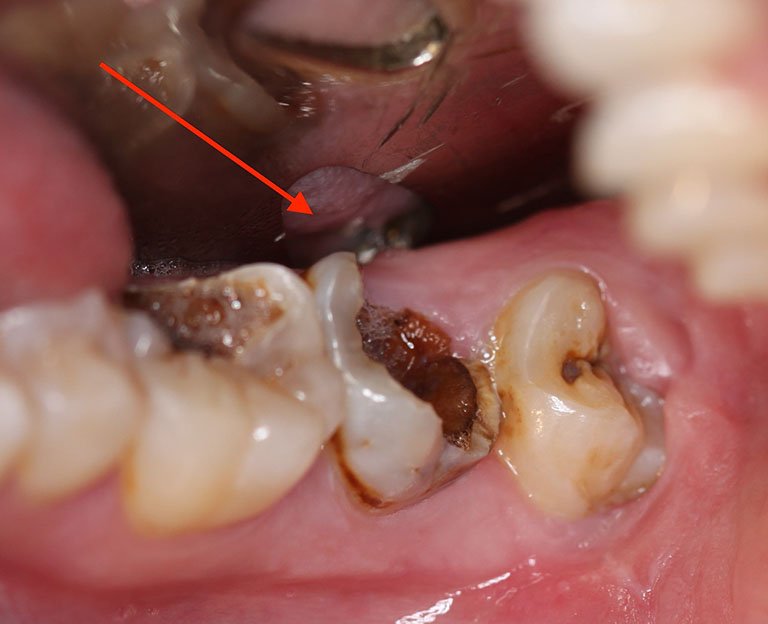

- Răng mọc chỉ một phần: Nghĩa là răng chỉ được lộ rõ một phần ở trên đường viền nước, phần còn lại vẫn mắc kẹt trong nướu hoặc xương hàm. Lúc này, răng số 8 sẽ gây ra nhiều vấn đề về răng miệng như sâu răng, sưng hoặc nhiễm trùng.

- Răng mọc nghiêng hoặc ngang: Về hình dáng bên ngoài, răng mọc nghiêng gần giống với răng chỉ mọc một phần. Răng chỉ mọc được một phần và phần còn lại bị mắc kẹt phía dưới, mọc ngang tạo áp lực cho các răng phía trước.

- Răng số 8 mọc sai hướng tạo khe với răng bên cạnh. Điều này sẽ tạo lỗ hổng để thức ăn nhét vào, hình thành vi khuẩn mà bàn chải khó làm sạch tới, gây sâu răng.